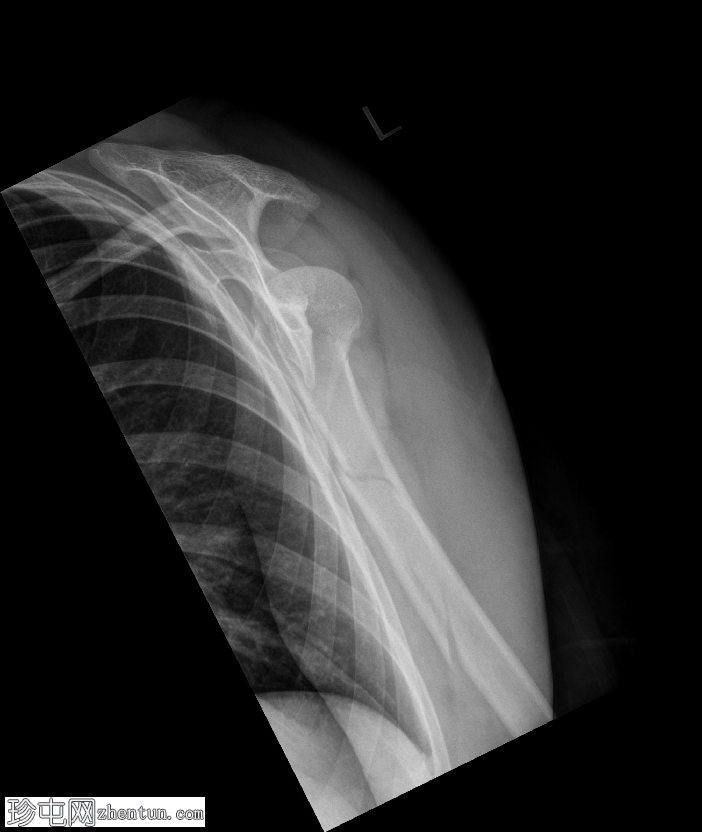

正位

肱骨近端粉碎性移位骨折,累及骨干近端半部、外科颈,并延伸至大结节。

肱骨头在肩关节内向下半脱位,肩峰肱骨间距增大。

肱骨头向下移位(假性半脱位)是肱骨近端骨折常见的继发性表现。它提示关节积液、关节积血或暂时性关节囊松弛,而非肩关节真正的不稳。手臂负重和肌肉张力下降(尤其是三角肌和肩袖肌群)共同导致肱骨头相对于肩胛盂位置下移<sup>1-3</sup>。

这种表现不应与真正的肩关节脱位混淆,因为在Y形位或轴位影像上,肱骨头仍与肩胛盂保持正确的对位。随着关节液的吸收和肌肉张力的恢复,这种情况通常会自行缓解。识别这种暂时性的良性表现对于避免不必要的复位手术至关重要。

在本病例中,肱骨头位置下移反映了由急性近端肱骨骨折引起的关节积液所致的假性半脱位,而没有真正的脱位证据。